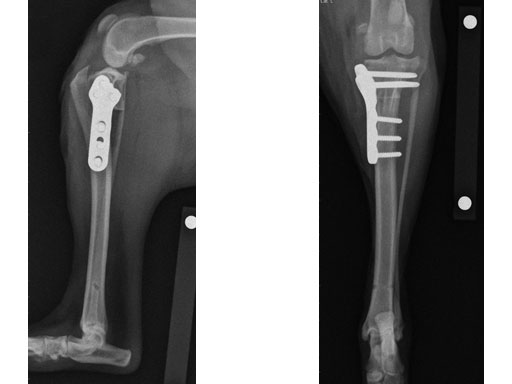

Case 1: Two-year-old Labrador Retriever

2-years-old Labrador Retriever, 30 kg, female. Chronic lameness in both hind limbs, chronic bilateral cranial cruciate ligament tears, with subsequent stifle joint instability and degenerative joint disease. At that time, she was more clinically lame on the left hind limb, and a surgical correction was subsequently performed on this limb. X-rays of the stifle joint revealed the degenerative joint changes and an effusion; the tibial plateau slope was 20. In addition, the x-rays confirmed that there was a slight amount of tibial torsion that also was observed clinically, accounting for a slight internal rotation of the distal limb. Radiographically, this could be assessed by a 4 mm shift of the normal point of intersection of the medial aspect of the calcaneus with the deepest point of the talar sulcus.

The stifle joint was surgically explored. All remaining remnants of the torn cranial cruciate ligament were debrided; in addition, the caudal pole of the medial meniscus was torn/crushed, and a partial meniscectomy of the damaged portion was performed. A TPLO plate 3.5 was applied to stabilize the fracture. The plate was applied in a neutral fashion. Postoperative x-rays revealed a tibial plateau angle of 5, and a correction of the torsion to 0 mm.

Follow-up x-rays at 8 weeks postoperatively revealed that the osteotomy had healed, and the dog was doing very well. The identical procedure was performed on the opposite stifle joint 2 months later. Healing was again obtained 8 weeks postoperative. Presently, the dog is about 1 year postoperatively and functioning very well.